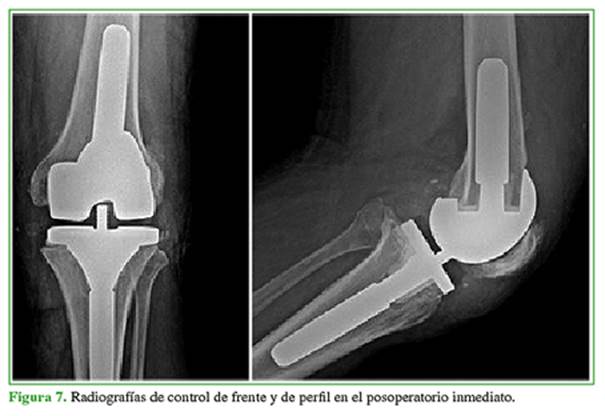

Hombre de 54 años, con hipertensión arterial, obesidad mórbida y exfumador. En otro Centro, había sido sometido a un reemplazo total de rodilla por genu varo artrósico, en diciembre de 2016. Tuvo una infección aguda de la prótesis con una fístula en el tercio distal de la cicatriz quirúrgica (Figura 1A), por lo que requirió una limpieza quirúrgica y conversión a un espaciador, en junio de 2017, sin rescate de germen (Figura 1B y C). A las tres semanas de la operación, en el examen físico, se observó un área de necrosis de 2 x 3 cm en la zona de la fístula inicial (Figura 1D).

Con parámetros clínico-humorales de remisión de la infección3 y tras haber logrado una cobertura y una cicatrización adecuadas, se realizó la conversión a prótesis de rodilla en enero de 2018 (Figura 7).